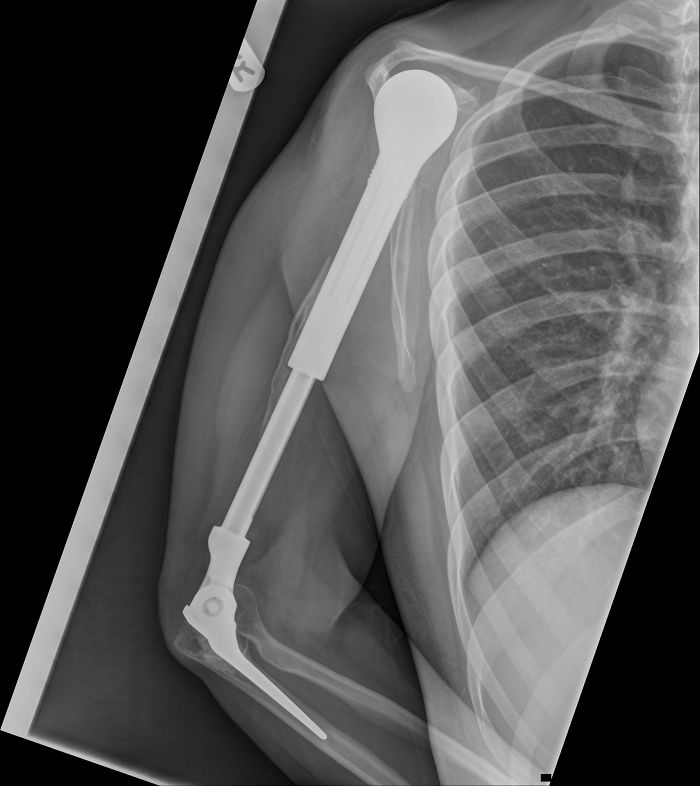

X-Ray Of My Metal Arm

X-Ray Of My Arm After Amputation, Thanks To Driver Who Fell Asleep At The Wheel